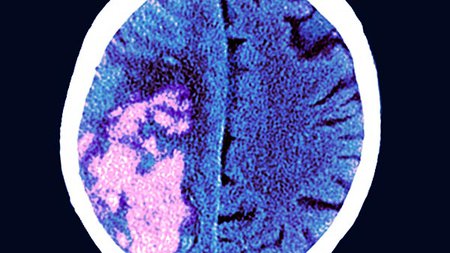

At Northside Hospital, our neurology services bring our teams together for accurate, rapid response to conditions impacting the brain, spinal cord and nervous system. If you are having any neurological issues, our team can help identify the problem – and provide the most appropriate care.

Northside’s neurology experts are on the front lines when it comes to stroke prevention, diagnosis, treatment and management. In fact, the Northside Hospital Stroke Center is an Advanced Primary Stroke Care Center of Excellence . At Northside, we provide comprehensive stroke care, including: